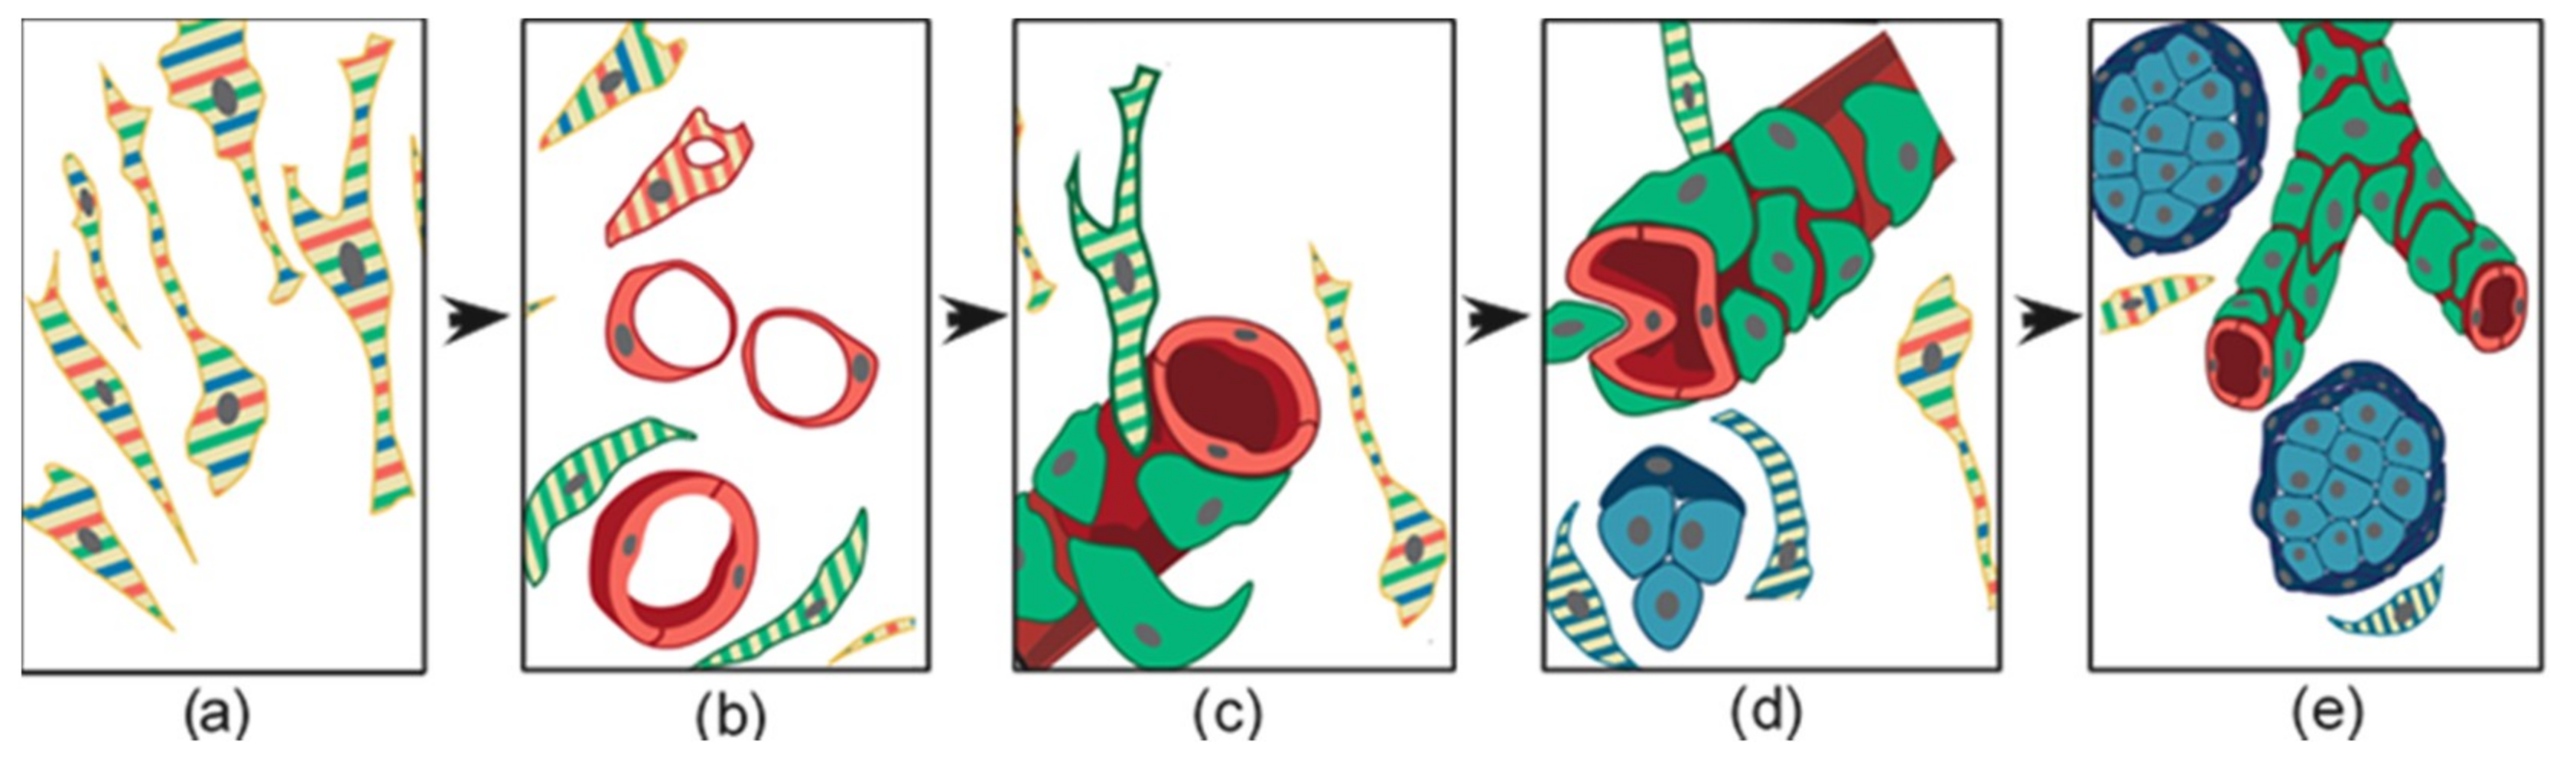

2. The Physiological Model of Carotid Body Hyperplasia Under Chronic Hypoxia May Illuminate Paraganglioma Development

4. Ultrastructural and Immunomorphological Relationships Between the Vascular and Neural Compartments of Head and Neck Paragangliomas

6. Constitutive Notch Signaling in Head and Neck Paraganglioma

7. Patient-Derived Head and Neck Paraganglioma Cultures Exhibit a Multipotent Mesenchymal-Like Phenotype